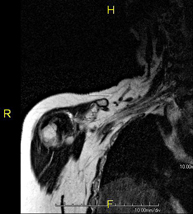

- RM Hombro

Exploración para el estudio de lesiones en tendones, músculos y articulación. Su principal utilidad reside en diagnosticar las lesiones de los tendones del manguito rotador. Tiene una duración aproximada de 20 minutos. No emplea radiación ionizante. - RM Brazo